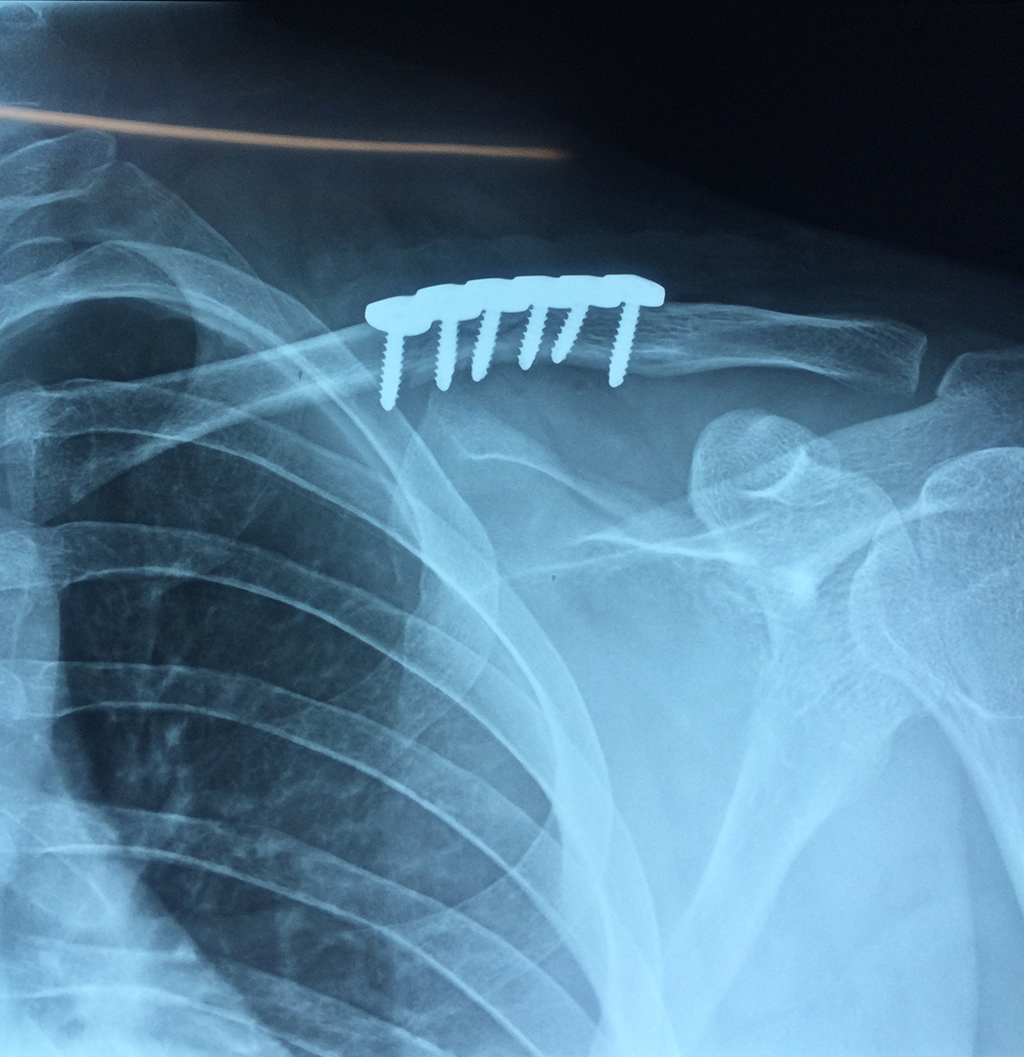

Cirugias en El Salvador - Clavícula

La clavícula es un hueso largo, con forma de "S" itálica, situado en la parte anterosuperior del tórax. Junto con la escápula forman la cintura escapular. Se puede palpar por toda su longitud y se extiende del esternón al acromion de la escápula, siguiendo una dirección oblicua lateral y posterior.

Se considera el único medio de unión entre el miembro superior y el tórax. A pesar de su aspecto, similar al de un hueso largo, posee una estructura semejante a la de un hueso plano, ya que carece de epífisis y de diáfisis, lo que la harían entrar dentro de la clasificación de hueso largo. Carece de un canal medular propiamente dicho.